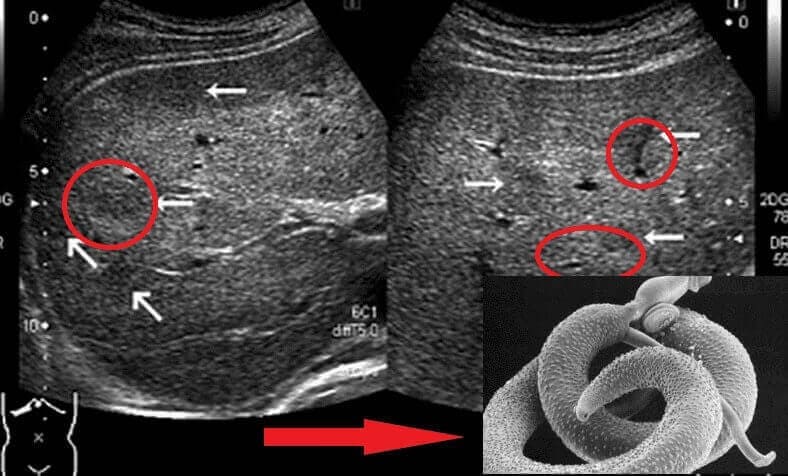

Съществуват десетки видове паразити, някои са дълги червеи, които могат да се открият по-лесно, но други са микроскопични и пътуват през кръвообращението, бавно отравяйки тялото ти с токсините си.

Аз също работя в областта на здравеопазването. Има хора, които не вярват, докато не го видят под микроскопа. Прикачвам снимка от лабораторията (ужасно е, но е истинско).